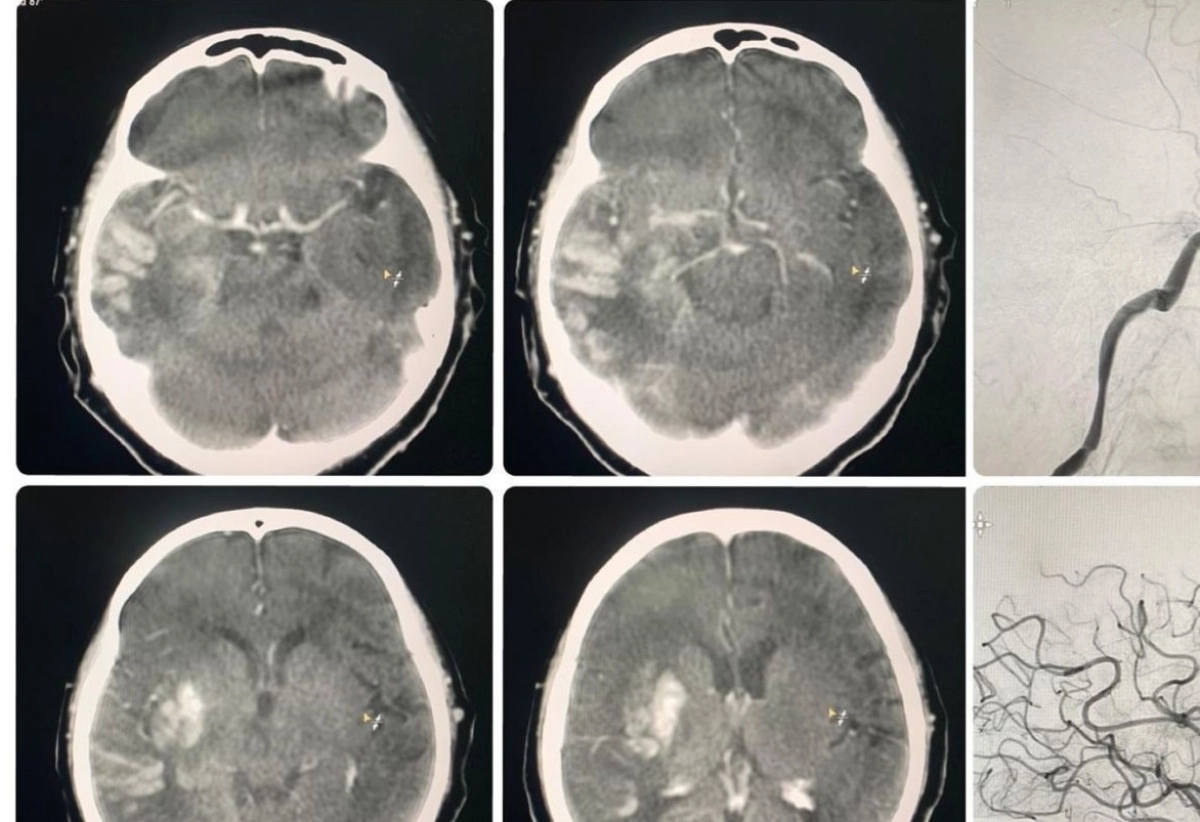

«Пациентка поступила с клинико-неврологической симптоматикой ишемического инсульта в бассейне правой средней мозговой артерии: левосторонний гемипарез, центральный парез лицевой мускулатуры слева, нарушение речи — дизартрия. Время начала заболевания — 1 час. В экстренном порядке проведена операция — селективная церебральная ангиография, где выявлена картина острой окклюзии (тромбоз/тромбоэмболия) правой внутренней сонной артерии на уровне офтальмического сегмента», — рассказал историю болезни заведующий отделением сосудистой нейрохирургии ГКБ №7 Алматы Рауан Кастей.

Специалист не исключает того, что тромб мог привести к тяжелым последствиям и даже летальному исходу. Далее проведена рентгенэндоваскулярная механическая тромбаспирация тромба из правой внутренней сонной артерии с применением нововнедренного в больнице аспирационного катетера RED72 вместо ранее использовавшегося ACE62.  Нейрохирурги отмечают, что преимущество нового катетера — увеличенный внутренний просвет, обеспечивающий наиболее высокую силу удаления тромба, улучшенное гидрофильное покрытие для плавного отслеживания и более дистального прохождения. В совокупности это дает достижение желаемого результата.

В сообщении больницы говорится, что данное внедрение вывело на новый уровень качество оказания высокотехнологичной медицинской помощи пациентам.Операция прошла успешно, осложнений и рецидивов не было. Проведенная контрольная ангиограмма подтвердила полное восстановление кровообращения в бассейнах правой средней мозговой артерии и правой передней мозговой артерии.